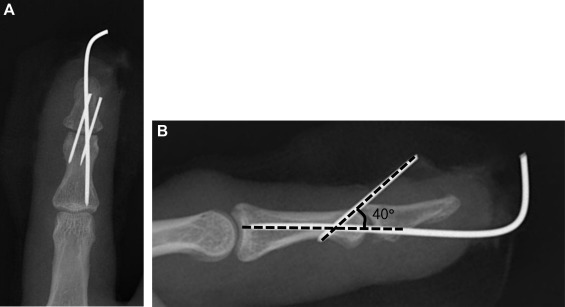

격투기 선수 출신의 자수성가 인물은 젊을 적 경기 중에 자기 오른손에 골절이 오면, 남은 왼손과 발차기를 이용해서 싸움을 이어나갔고.